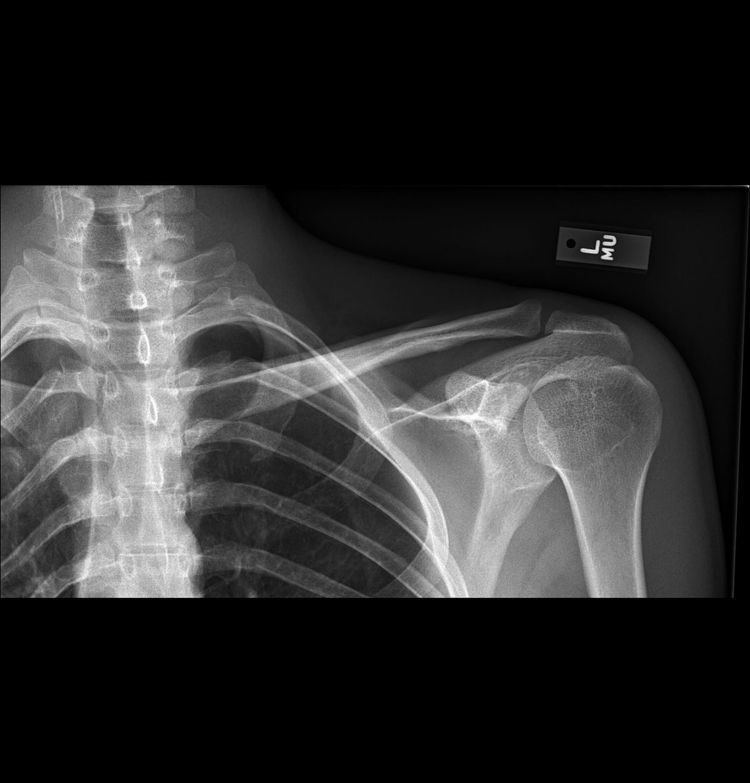

Companion shadow is a term used in describing radiographs that denotes the appearance of a smooth, homogenous, radiodensity with a well-defined margin that runs parallel with a bony landmark. Companion shadows represent soft tissue that overlies the respective bony landmark in profile. They are not seen in every radiograph and can be misinterpreted as pathology.